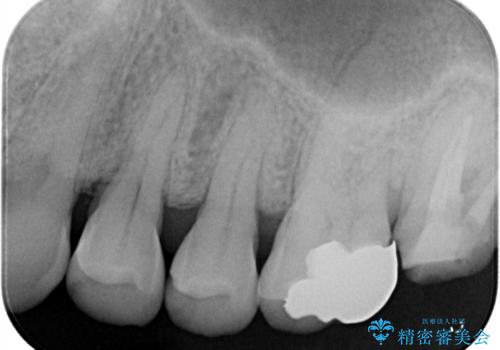

レントゲン上にて、左上6番遠心にインレーと歯質の不適合を認めます。

健全歯質の残存量から、クラウンでのやり替えを提案しオールセラミッククラウン(スタンダード)でのやり替えとなりました。